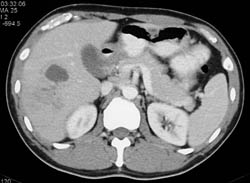

Hepatic Congestion